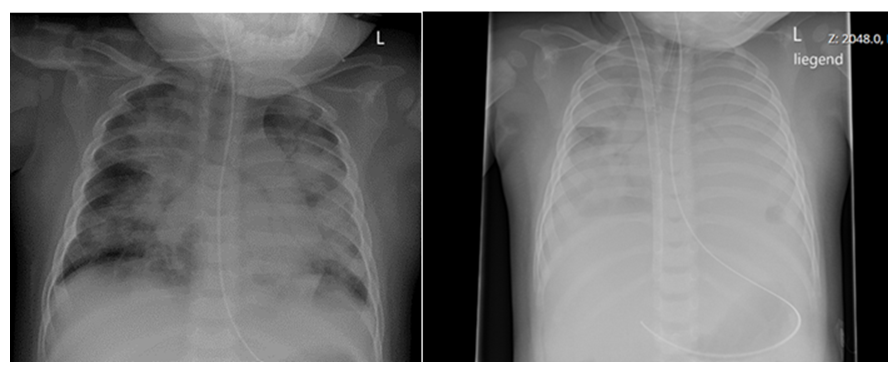

Figure 1: Chest X-ray at admission to PICU with signs of severe PARDS (left side) and X-ray after jugular VV-ECMO cannulation via dual-lumen cannula (right side) of the same patient following rapid respiratory deterioration few hours later.

Until now there is no clear understanding of the underlying pathophysiology in DS with respiratory infections and severe clinical course leading to PARDS. In our case series we demonstrate four cases of severe multi-organ dysfunction following respiratory infections in children with SCN1A related Dravet syndrome. Patients suffered life-threatening complications including respiratory and kidney failure as well as long-term neurologic sequelae. We were surprised by the rapid progression and the severity of the patients’ course (figure 1). Pathogens were identified in two of the patients, differed from patient to patient (Influenza type B, enterovirus) and were not age-dependent. It is likely that DS patients’ pulmonary vulnerability is not limited to a special pathogen or age-group but might be more likely related to its underlying genetic constellation. The gene SCN1A is primarily expressed in the brain and also in the lungs, thus might play a crucial role in pathogenesis of severe pulmonary disease [5].